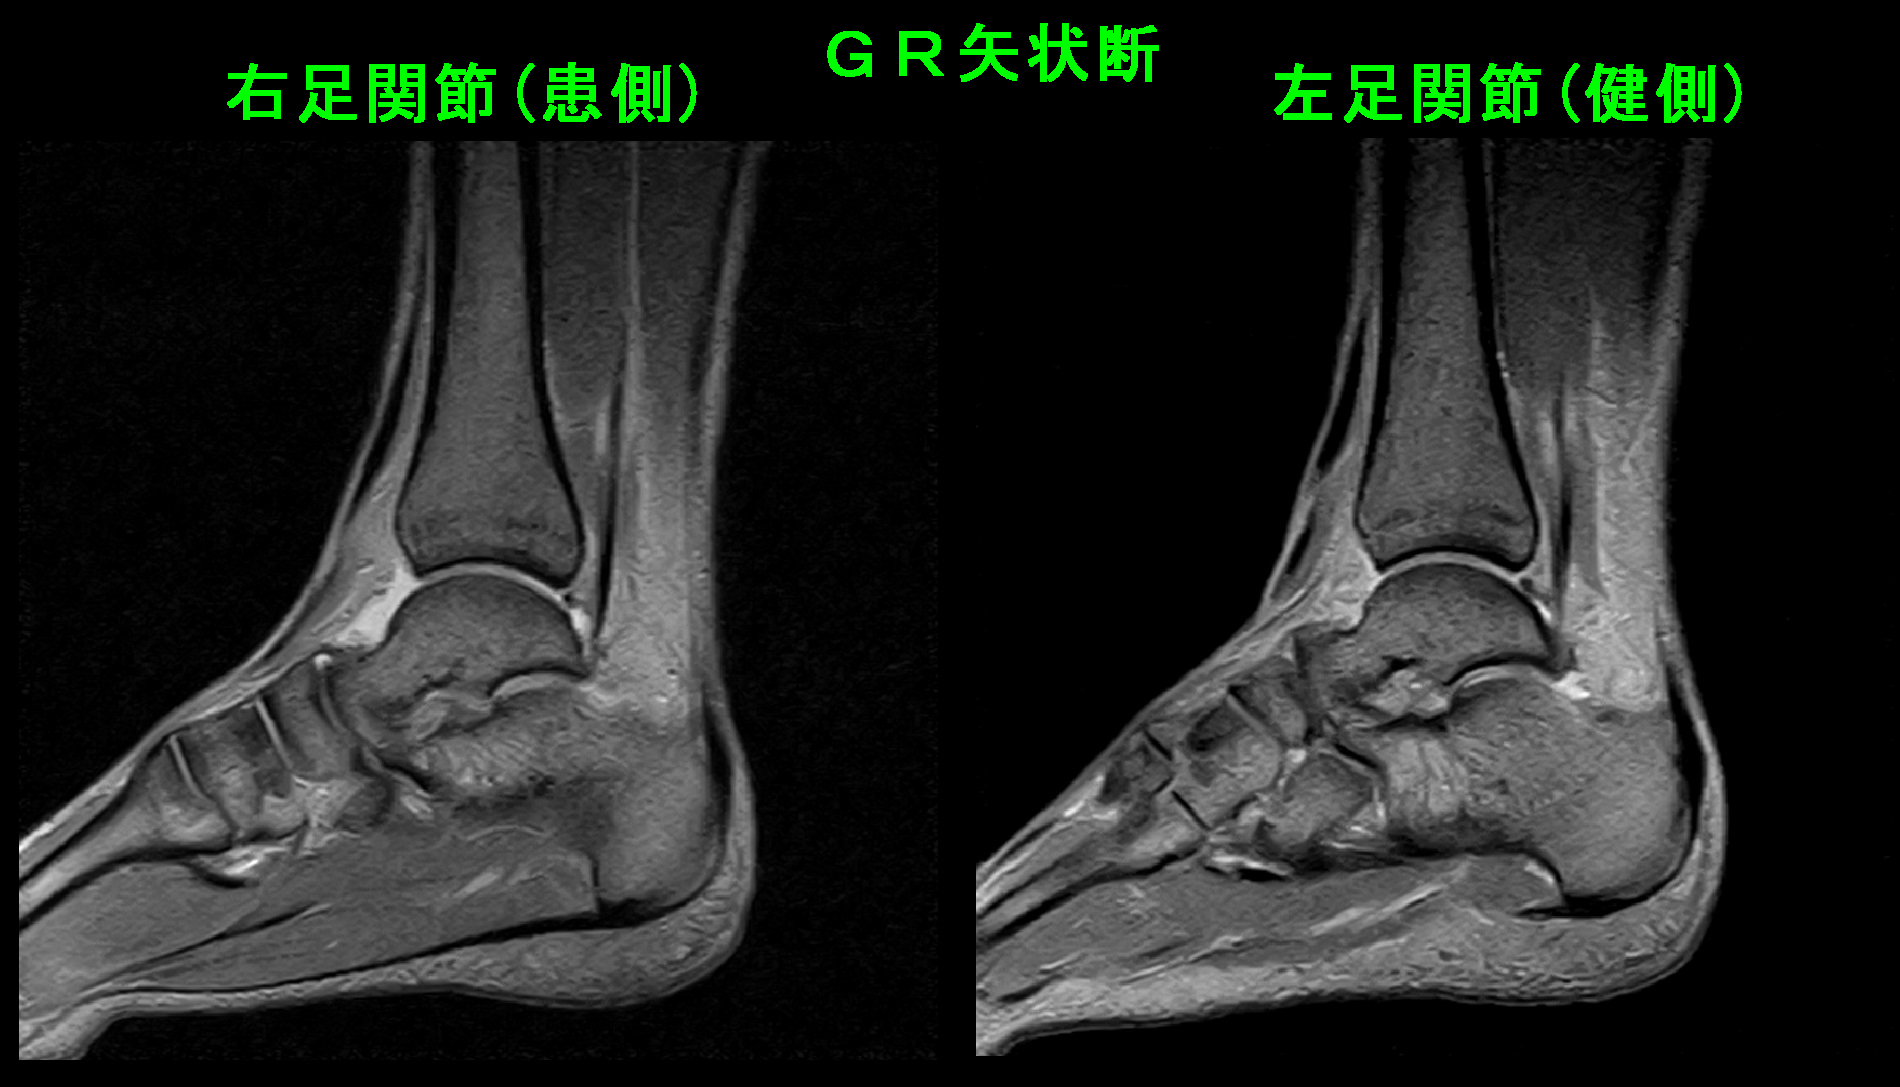

次は14才中学2年の陸上部のハードルの女子選手です。平成26年9月6日のリレーの練習で右足関節を捻挫し、かろうじて歩行ができる状態で当日受診されました。1週間後の9月13日に新人戦の県北大会があり、ハードルとリレーに出場予定だそうです。

14才女 Xp1.jpg

右足関節の外側は左足関節に比して腫れています。普通なら出場は無理と判断されるでしょう。私はMRI検査を行い、骨に損傷がなければ、左足関節の注射の治療で出場できるかもしれないと説明しました。

14才女 MR1.jpg

MRI検査(骨が黒く見えるSTIRという条件)では患側の右足関節には骨の損傷はなく、関節部の白さが広がっており(赤矢印)、関節内に出血を認める関節炎の所見です。健側の左足関節の距骨の後ろ側が軽度高輝度を示しており、こちらはケガしていないのですから、元々の運動による痛みを伴っていない疲労骨折の前駆状態と理解されます。このようなことはしばしば見られるものです。

14才女 MR2.jpg

バレーボールの男子生徒のように足関節を斜めに切るMRI所見(GR条件)では前距腓靭帯が断裂しています(赤矢印)。この状態で全力で走れるようになるには最低で4週間ぐらいはかかるものです。しかし、本人は大会に出たいはずで、私は関節内注入療法をすれば出場できるかもしれないと提案しました。本人も同意して関節内注入を行い、簡易タイプのギプスシーネ固定を行い、投薬は10日分処方し大会終了まで服薬を継続し、3日間固定した後にシーネを外して練習を開始してみる治療方針としました。